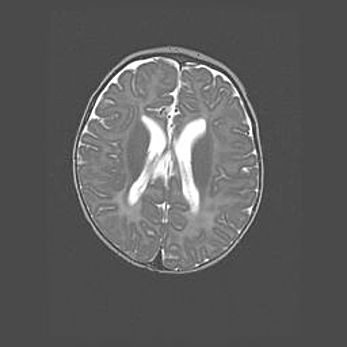

Сообщающаяся гидроцефалия. Кистозная энцефаломаляция головного мозга.

Возраст: 3 месяца 4 дня

Вес: 3100 г

Пол: женский

Окружность головы: 34 см

Срок гестации: 31 неделя

Кистозная энцефаломаляция головного мозга - одна из форм поражения головного мозга в детском возрасте. Характеризуется возникновением множественных и распространённых кист в коре, белом веществе и подкорковых образованиях головного мозга у плодов, новорождённых и детей раннего возраста. Развитие кистозной энцефаломаляции связано с внутриутробной асфиксией и гипотонией, родовой травмой, тромбозом синусов, пороками развития сосудов, инфекциями, сепсисом и другими причинами. Наиболее значимые инфекционные агенты: вирусы простого герпеса, цитомегалии, краснухи, токсоплазмы, энтеробактерии, золотистый стафилококк и другие.